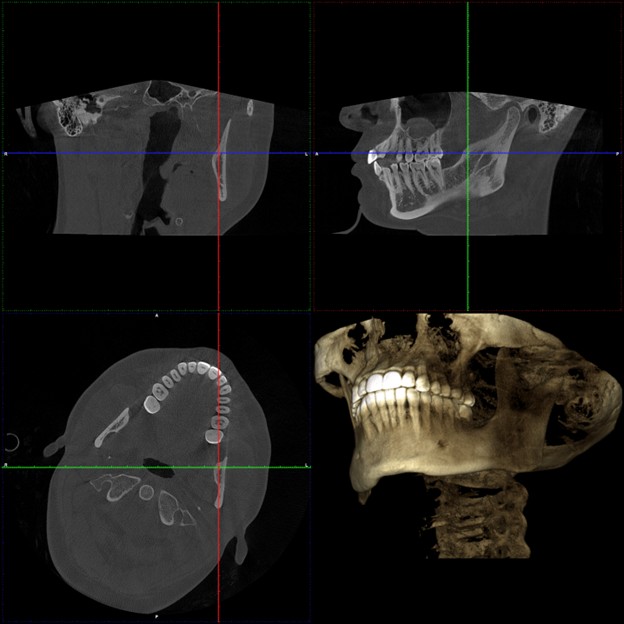

TMJ: Detailed Diagnostic Cone Beam Computed Tomography CBCT

The Cone Scan Radiograph or CBCT we have is state of the art and gives us a .7mm voxel size. (voxel is a 3d pixel). This machine has revolutionized the way that we look at TMJ problems.

Our first important step is proper diagnosis with a well taken CBCT.